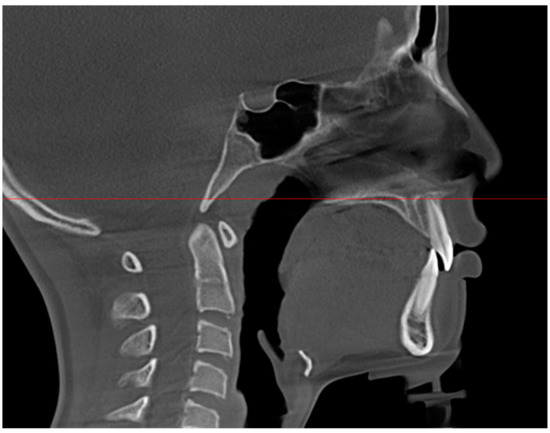

2.2. Data Acquisition and Measurements